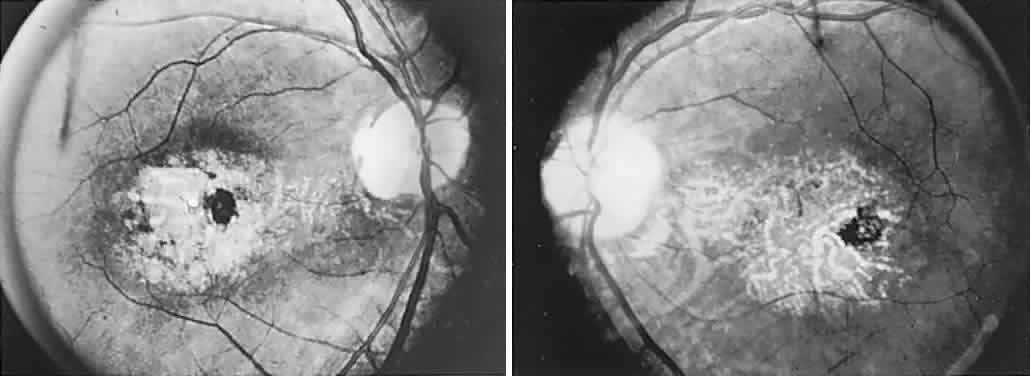

The retinal variety may be admixed in a person who suffers the more conventional attacks of migraine. It is presumed that vasospasm in the retinal circulation determines transient hypoxia, perhaps somewhat similar to the visual cortical event. On rare occasions, the fundus has been examined during typical retinal migraine episodes, and arterial constriction has been described. Wolter and Burchfield106 photographically documented such an episode and demonstrated mild “retinal edema”; vessel narrowing is also evident (Fig. 8). Fortunately, permanent complications of retinal migraine are rare. These may take the form of central retinal artery occlusion or ischemic papillopathy (see Volume 2, Chapter 16); nerve fiber bundle visual field defects may be demonstrated (Fig. 9).

Fig. 8. Retinal migraine. A. During amaurotic episode. Note the dusky appearance of the fundus, increased retinal sheen (possibly edema), and dark narrowed veins (arrows). The disc is also hyperemic. B. Fundus after episode. Compare paired arrows. (Courtesy of Dr. J. Reimer Wolter)

Fig. 9. An 18-year-old student with recurrent episodes of left retinal migraine. After a typical attack, he noted an inferior field defect. A. Fundus shows a defect in the superior arcuate nerve fiber bundle (between arrows: compare fiber layer below disc). B. Visual field defect corresponds to a retinal nerve fiber layer defect.